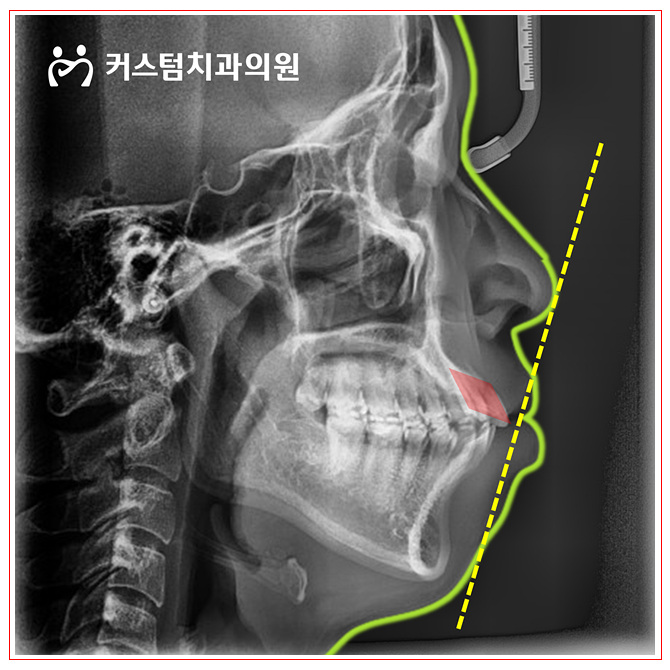

원미구치과 돌출입을 갖고 계시다면

원미구치과 돌출입을 갖고 계시다면 여러분, 안녕하십니까. 베테랑 교정전문의가 처음부터 끝까지 책임지고...